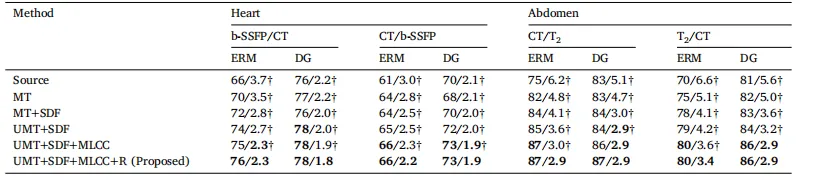

Table 5Comparison of the continual test-time adaptability of each model (with CiDG source model). The same source model was used by all benchmarked methods. ATTA was excludedfrom the comparison as it was designed for episodic test-time adaptation. Each cell presented each model’s running/final Dice scores (in %) for each scenario. Equal (in italics)or higher final Dice scores (in bold) indicate a model’s suitability for continual test-time adaptation.

表 5 比较每个模型(使用 CiDG 源模型)的持续测试时适应性。所有基准方法均使用相同的源模型。由于 ATTA 被设计用于情节性测试时适应(episodic test-time adaptation),因此未纳入比较。每个单元格表示每个模型在每种场景下的运行/最终 Dice 分数(以 % 为单位)。相等的(斜体)或更高的最终 Dice 分数(粗体)表明该模型适合持续测试时适应(continual test-time adaptation)。

Table 6Ablation study of the proposed method with both ERM and DG-trained source models on representative datasets. Each component is graduallyadded to demonstrate its contribution. Here, MT denotes mean teacher, SDF refers to the signed distance field, UMT stands for uncertainty-awaremean teacher, MLCC indicates multi-level cross-task consistency, and R is short for weight reset. † denotes statistical significance between theDice/ASSD score of an ablated and that of the proposed method (𝑝 < 0.05). Best results marked in bold

表 6 关于所提出方法的消融研究,使用 ERM 和 DG 训练的源模型在代表性数据集上进行。逐步添加每个组件以展示其贡献。表中,MT 表示均值教师(mean teacher),SDF 表示符号距离场(signed distance field),UMT 表示基于不确定性的均值教师(uncertainty-aware mean teacher),MLCC 表示多层次跨任务一致性(multi-level cross-task consistency),R 表示权重重置(weight reset)。† 表示消融方法的 Dice/ASSD 分数与所提方法之间具有统计显著性 (𝑝 < 0.05)。最佳结果用 粗体 标出。